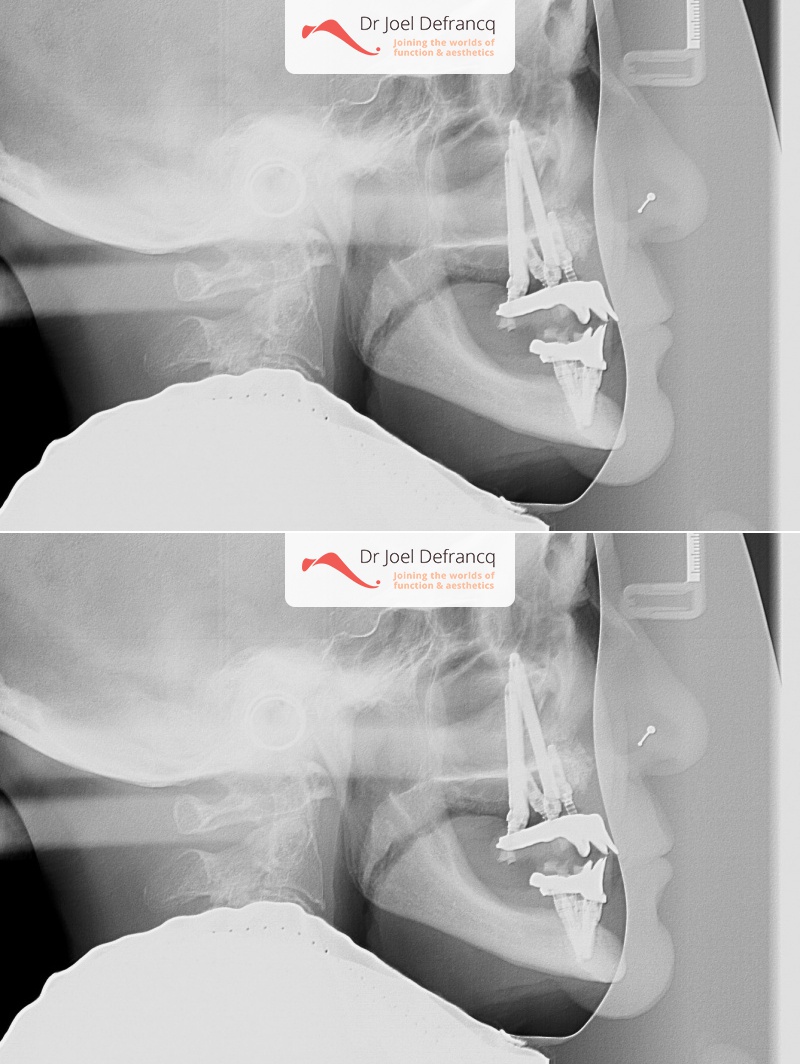

Behandeling tandheelkundige implantaten

- Vaste tanden op implantaten (bovenkaak)

- Vaste tanden op implantaten (onderkaak)

- Zygoma implantaten